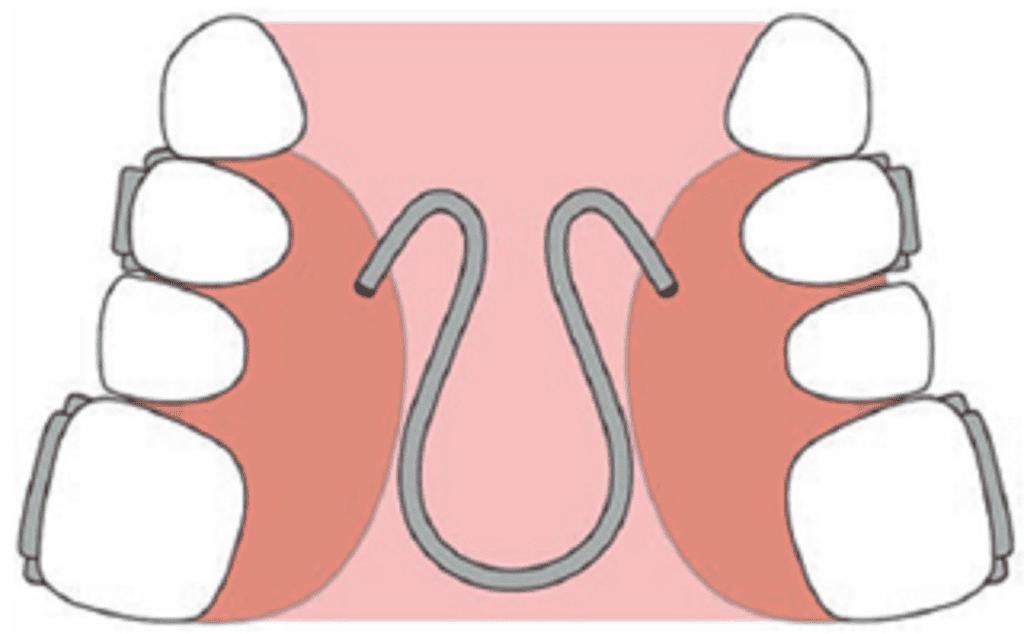

c) Removable quad helix appliances

Removable quad helix is inserted into the lingual attachment (lingual sheath) which is welded or soldered to the molar band. This permits adjustment of the appliance outside the mouth.

Quad/ Tri/Bi Helix appliance

Quad helix was introduced by Robert M Ricketts.

The appliance is a precursor to the tri- and the bi-helix appliances. They are all named after the number of helices incorporated in the appliance.

Appliance framework ̶ The quad helix consists of four helices made of 0.038″ diameter wire (elgiloy or stainless steel wire), soldered to the molar bands. The length of wire increases the range of action and flexibility, and decreases the force levels. The tri- and the bi-helix appliances incorporate only three and two helices respectively.

It is a fixed appliance comprising stainless steel bands cemented onto the maxillary first molars and a standard stainless steel arch attached to the palatal surfaces of the teeth.

Parts of quad helix: (A) posterior helix, (B) palatal bridge, (C) anterior helix, (D) anterior bridge and (E) outer arm.

The quad-helix consists of two anterior and two posterior helices. The portion of wire in between the two anterior helices is called the anterior bridge and that connecting the anterior helices and the posterior helices is called the palatal bridge. The free ends that are usually adapted close to the premolar teeth are called the outer arms. The outer arms are soldered to the molar bands. The posterior helix should not extend more than 2 mm distal to the first permanent molar.

Activation – The appliance is capable of producing differential expansion i.e. it can be activated to produce expansion levels in the premolar and molar regions.

It can be activated prior to cementation of the bands by stretching the molar bands apart or in the mouth with the use of three-prong pliers.

- In the anterior bridge: Results in expansion in the molar region

- In the palatal bridge: Derotation and expansion of molar on the same side and distalization of molar on the opposite side

- Outer arms are activated to expand canines and premolars

- Opening of posterior helix expands the buccal arm

An initial expansion of 8 mm will produce 14 oz of force. Average force is 200–400 g depending upon the amount of expansion or activation. The expansion of the steel arch (normally 10 mm before insertion) exerts a lateral force on the teeth, resulting in a predominant transverse dentoalveolar expansion of the maxillary arch. If necessary, the appliance can be reactivated after 6 weeks. Once inserted, the appliance is not dependent on patient compliance.